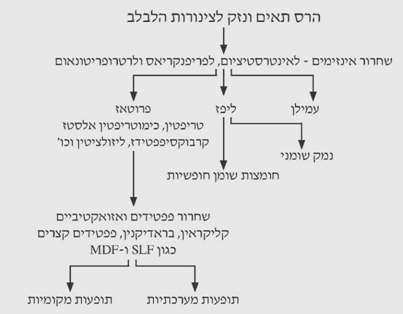

כל אלה גורמים לשתי תוצאות: הרס תאי לבלב והרס של צינורות הלבלב, ועקב כך שחרור אנזימים לאינטרסטיציום, מסביב ללבלב (Peripancreas) ולאחורי הצפק (Retroperitoneum). שחרור האנזימים גורם לתופעות מקומיות ומערכתיות (תרשים 1.9).

במשך שנים רבות סברו חוקרים שהטריפסין ואנזימים אחרים המפרקים חלבונים הם האחראים העיקריים לנזק המתרחש בלבלב בזמן התקף חריף. אך בשנים האחרונות נמצאו עדויות מעבדתיות שפוספוליפאז A, ליפאז ואלסטאז הם בעלי חשיבות רבה בפתופיזיולוגיה של המחלה. בנוכחות כמויות קטנות של מלחי מרה, תוקף הפוספוליפאז את הפוספוליפידים (לציטין), ואלה נקשרים לקרום התאים ויוצרים חומרים הממיסים את דופן התאים. הליזולציטין, הנוצר מפעילות של הפוספוליפאז A על מלחי המרה, עלול לגרום לנמק של הלבלב.

הטריפסין חשוב במקרים אלה, מכיוון שהוא גורם לאקטיבציה של הפוספוליפאז A. האלסטאז עלול לעכל את דופן כלי הדם ולגרום לדמם חריף.